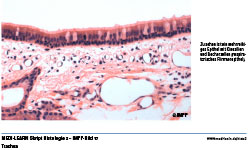

• Trachea